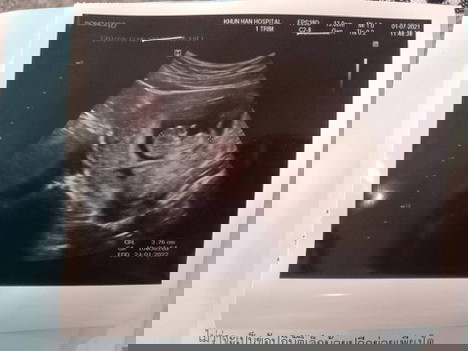

อายุครรภ์ของน้อง แม่ดูยังไงคะอ่านแบบไหนให้ได้11w1d. เค้าอ่านไม่เป็น เพราะของเราก็10w4d+-อยู่ข้างล่าง8d อ่ะ อ่านยังไงเค้างง😂

จากรูปu/s อ่านได้10w4d+- มีขนาด3.36cm มั้ยคะ ไม่รู้อ่านถูกรึเปล่า ถ้าใช่ก็ปกตินะคะ หมออาจจะบอกว่าน้องยังตัวเล็กอยู่มาก